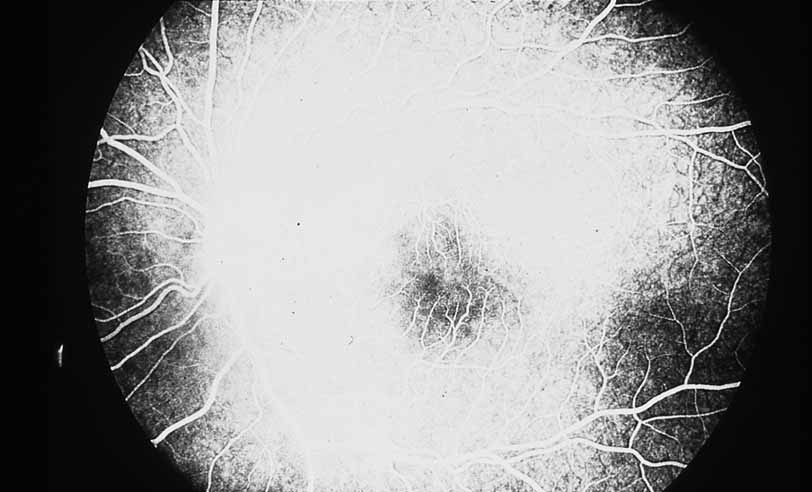

Fig. 12 Acute multifocal hemorrhagic retinal vasculitis. The patient later developed disk neovascularization with vitreous hemorrhage. Note the areas of neovascular leakage from the optic nerve.

Fig. 13 Acute multifocal hemorrhagic retinal vasculitis. The patient underwent scatter laser photocoagulation to the zones of retinal capillary nonperfusion, which resulted in regression of the neovascularization.